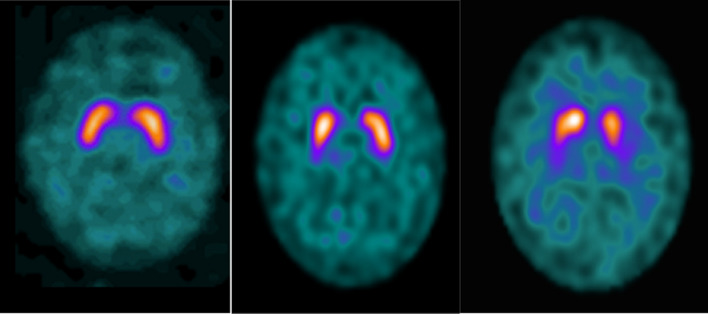

Seventy-four patients with symptoms of parkinsonism, who had undertaken routine SPECT-CT DaTSCAN, were included in the analysis. The scans were also subdivided into either degenerative parkinsonism (abnormal = 49), borderline (n = 14) or scan without evidence of dopaminergic deficit (SWEDD = 11) according to both visual assessment and specific binding ratios (SBR) by nuclear medicine consultants (Table 1). The scans were categorised as borderline if images visually suggested reduced DaTSCAN binding within the striatum, with either borderline or lower range of normal DaTQUANT SBR values (Fig. 2).

Fig. 2.

SWEDD (left), borderline (middle) and abnormal (right) [123I]Ioflupane (DaTSCAN) SPECT Scans. SWEDD demonstrates bilateral inverted comma shape representing the caudate nucleus (at the top) and putamen (at the bottom). Borderline image shows a suspicious “weak comma” on the right side of the brain scan but had normal SBR values. The abnormal scan shows an obvious left-sided “full stop”-shaped binding with diminished SBR in this area